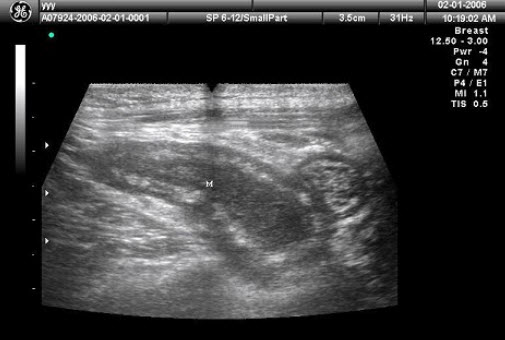

27、单项选择题 肝内血管纹理减少最常见于()

发现一侧乳房无痛性肿块3天,腋窝及颈部可触及数个黄豆大包块,乳腺超声声像图如上,最可能的诊断是()